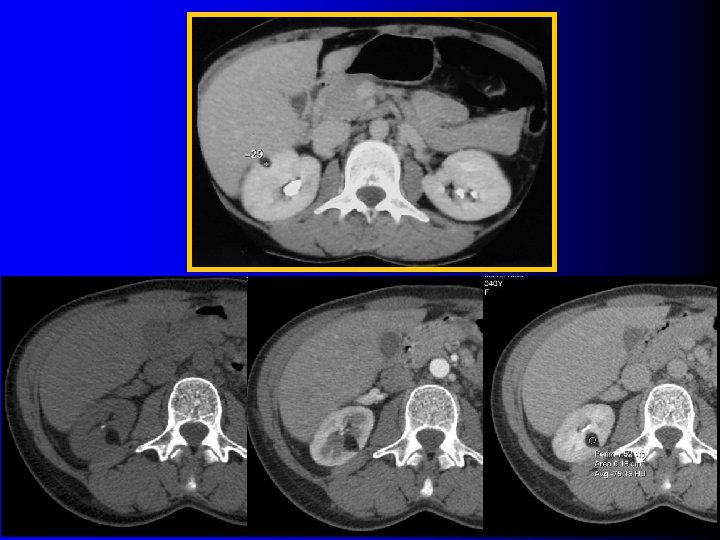

Tomodensitométrie Tumeur hypervasculaire avec plages de densité graisseuse (-10 UH à -100 UH) l l Intérêt : – Diagnostique – Thérapeutique : l Taille exacte l Localisation l Importance du contingent vasculaire l Technique d'examen rigoureuse: – Minimiser les effets de volume partiel l Coupes fines (millimétriques) l Examen sans injection

Tomodensitométrie Tumeur hypervasculaire avec plages de densité graisseuse (-10 UH à -100 UH) l l Intérêt : – Diagnostique – Thérapeutique : l Taille exacte l Localisation l Importance du contingent vasculaire l Technique d'examen rigoureuse: – Minimiser les effets de volume partiel l Coupes fines (millimétriques) l Examen sans injection

Tomodensitométrie l Meilleur seuil de densité ? – Simpson E & Patel U, Clin Radiol 2006; 61: 410 l 22 AML prouvés histologiquement l 3 seuils étudiés: 0 UH, -10 UH et -20 UH – 0 UH Se: 77% ; Spe: 97% – -10 UH Se: 73% ; Spe: 100% – -20 UH Se: 50% ; Spe: 100%

Tomodensitométrie l Meilleur seuil de densité ? – Simpson E & Patel U, Clin Radiol 2006; 61: 410 l 22 AML prouvés histologiquement l 3 seuils étudiés: 0 UH, -10 UH et -20 UH – 0 UH Se: 77% ; Spe: 97% – -10 UH Se: 73% ; Spe: 100% – -20 UH Se: 50% ; Spe: 100%